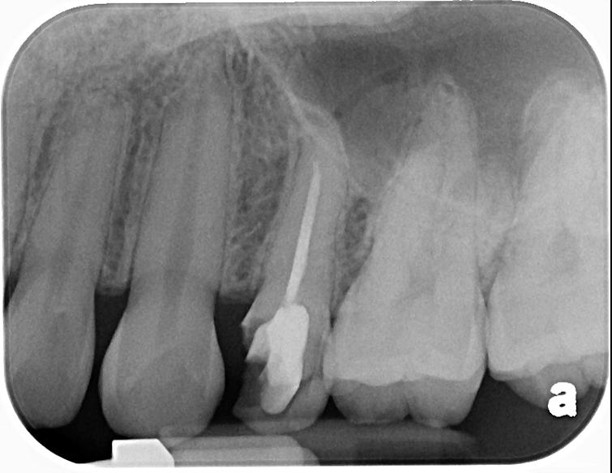

治療前,原根管治療已再污染

小臼齒顯微根管重治療